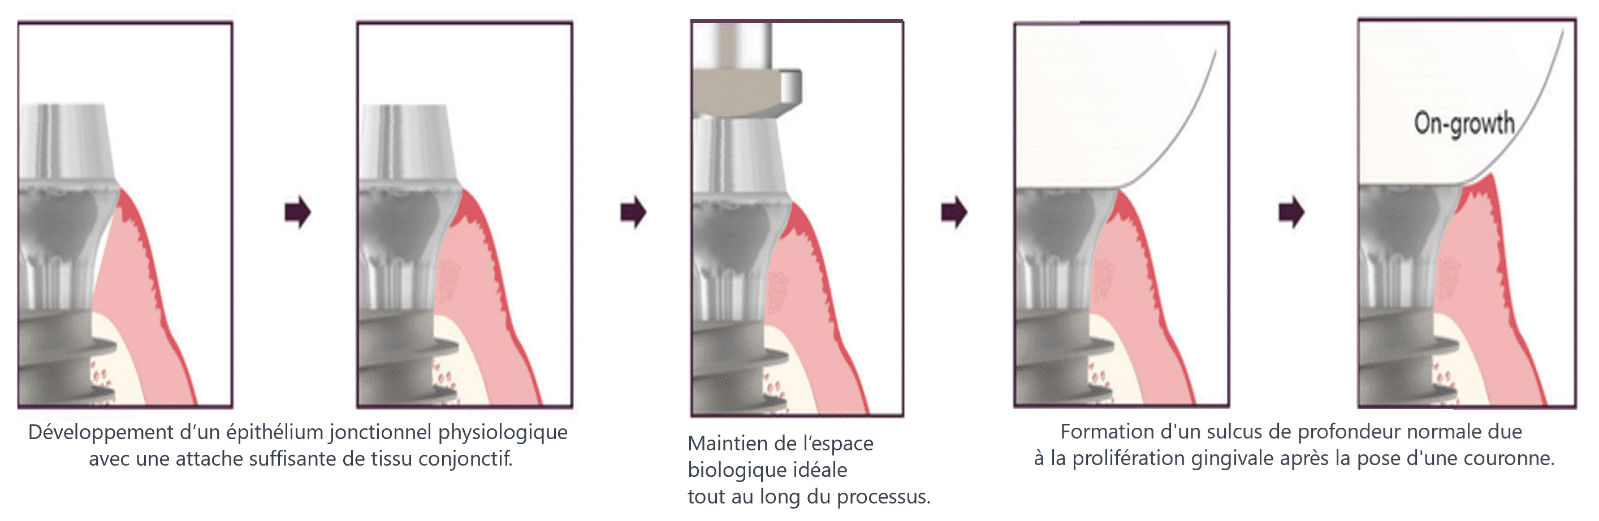

(Figure 5) Processus de prise d’empreinte et de mise en place de la couronne avec MagiCore.

En revanche, les implants MagiCore sont des implants au niveau des tissus avec une structure monolithique, ce qui élimine la présence de microgaps et de micromobilité. L’étanchéité entre le tissu conjonctif et le Magic Cuff n’est pas compromise lors de la prise d’empreinte ou du processus de pose de la couronne (figure 5).

Ainsi, comme le montre la figure 2-2, même en cas de modification de la forme de la gencive, le scellement du tissu conjonctif formé initialement reste solide et sûr. De plus, étant donné que la chirurgie peut être réalisée sans lever de lambeau, la continuité de la gencive est maintenue, ce qui favorise une cicatrisation et un remodelage plus rapides du tissu conjonctif.